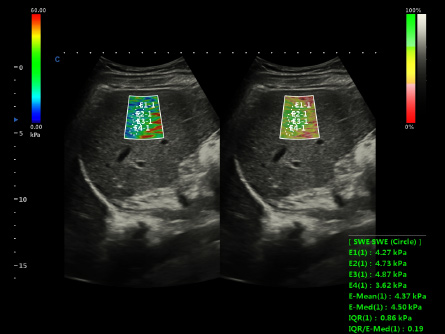

Experimenta la excelencia en radiología con los equipos de ultrasonido de CHISON. Nuestros dispositivos de alto rendimiento ofrecen imágenes de precisión y características avanzadas, satisfaciendo las demandas de los radiólogos de todo el mundo. Desde la visualización clara de tejidos blandos hasta escaneos rápidos, nuestras máquinas optimizan el flujo de trabajo, garantizando la precisión diagnóstica. Explora nuestras soluciones de ultrasonido de radiología mejor valoradas para una atención superior al paciente y satisface las necesidades de tus pacientes con confianza.

Dedicated Features